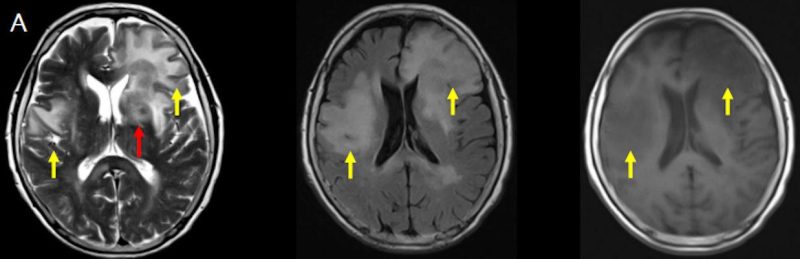

- (A) Her iki periventriküler beyaz cevherde aksiyel T2A, FLAIR serilerde hiperintens, T1A hipointens geniş ödem alanları (oklar) izlenmektedir. Sol frontalde T2A’da hipointens kitle lezyonuna (ok) dikkat ediniz.

- (C) Difüzyon ağırlıklı görüntülerde sol frontaldeki kitle lezyonunda difüzyon kısıtlama bulgusu (oklar) mevcut olup perfüzyon MRG’de rCBV haritasında belirgin perfüzyon artışı izlenmemektedir (ok).

- Genellikle supratentoriyal alanda, bazal ganglion, periventriküler beyaz cevher, orta hat ve korpus kallozum vb. yerleşme eğiliminde tek veya multipl kitleler şeklinde görülür.

- Kitleler çoğunlukla solid ve homojendir.

- MRG’de, lenfomalar tipik olarak T2A sekanslarda hipointens olup DAG’de belirgin difüzyon kısıtlanması gösterirler.

- T2 sinyali belirgin düşük olgularda b=1000 görüntülerde hipointens görünüm izlenebilir ve T2 kararması (T2 black-out) etkisi olarak adlandırılan bu durum yanlış yorumlamalara yol açabilir. Bu nedenle gerçek difüzyon kısıtlamasını değerlendirmede ADC haritaları daha güvenilirdir.

- Perfüzyon MRG’de düşük-orta düzey CBV değerleri izlenir. Lenfomalarda düşük CBV değerleri, kötü prognoz göstergesidir.